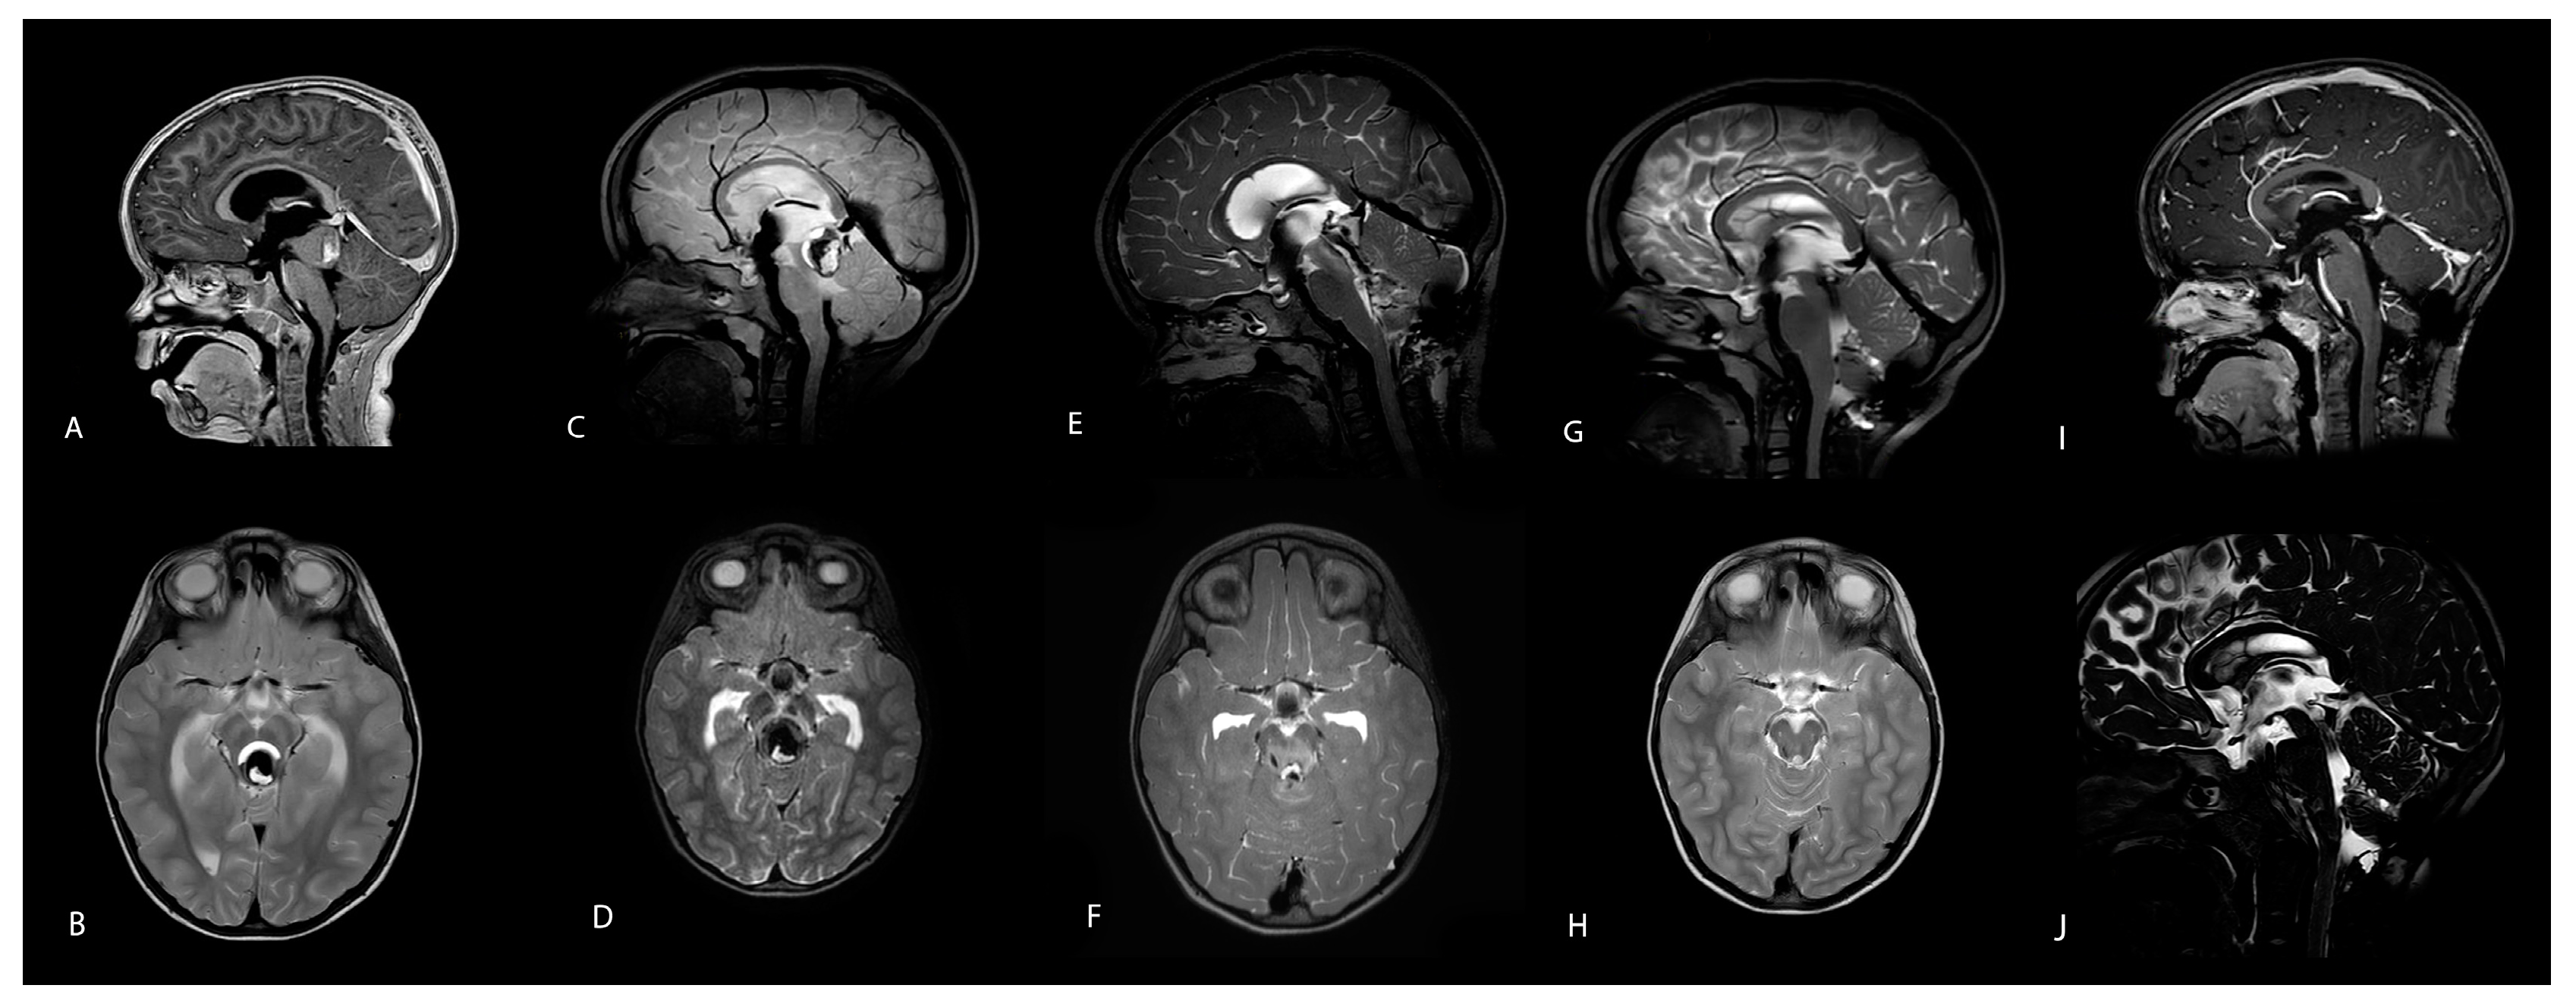

2. Case Description